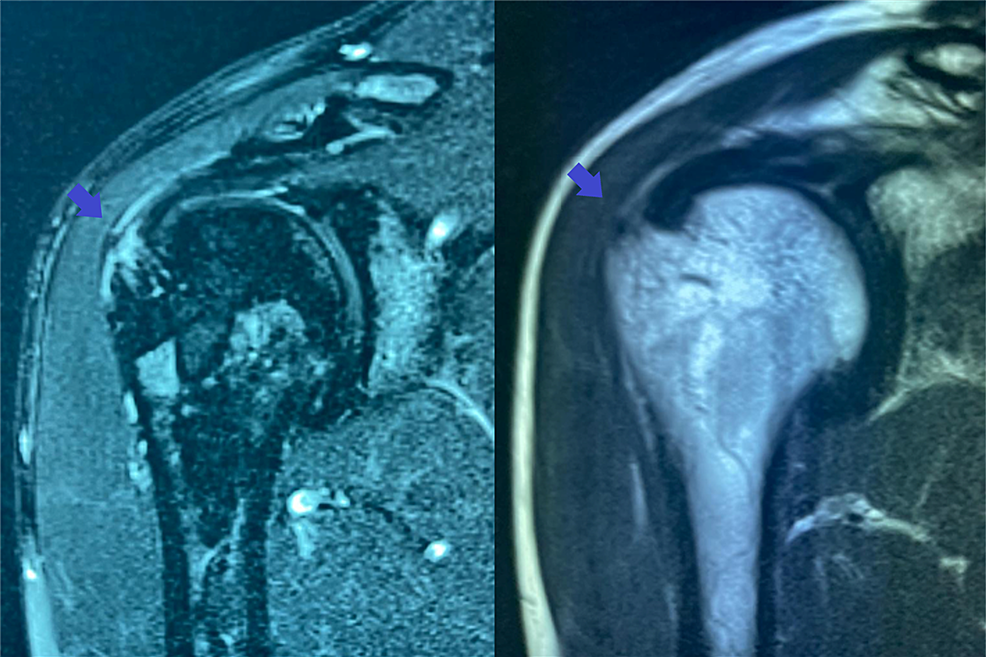

From www.cureus.com

Cureus UltrasoundGuided Injection of a Hyaluronic Hyaluronic Acid Injection Rotator Cuff The use of ha in patients with rotator cuff tears improve vas and functional score in all trials that we have analyzed. The present study demonstrated that pain and shoulder function were improved significantly after sh treatment. A combined injection of hyaluronic acid and prp (weekly × 4 weeks) into the subacromial space was found to significantly. Hyaluronic Acid Injection Rotator Cuff.

UltrasoundGuided Injection of a Hyaluronic Acid Hyaluronic Acid Injection Rotator Cuff The present study demonstrated that pain and shoulder function were improved significantly after sh treatment. The use of ha in patients with rotator cuff tears improve vas and functional score in all trials that we have analyzed. A combined injection of hyaluronic acid and prp (weekly × 4 weeks) into the subacromial space was found to significantly. Hyaluronic Acid Injection Rotator Cuff.

From www.researchgate.net

(PDF) UltrasoundGuided Injection of a Hyaluronic Hyaluronic Acid Injection Rotator Cuff A combined injection of hyaluronic acid and prp (weekly × 4 weeks) into the subacromial space was found to significantly. The use of ha in patients with rotator cuff tears improve vas and functional score in all trials that we have analyzed. The present study demonstrated that pain and shoulder function were improved significantly after sh treatment. Hyaluronic Acid Injection Rotator Cuff.

UltrasoundGuided Injection of a Hyaluronic Acid Hyaluronic Acid Injection Rotator Cuff The use of ha in patients with rotator cuff tears improve vas and functional score in all trials that we have analyzed. The present study demonstrated that pain and shoulder function were improved significantly after sh treatment. A combined injection of hyaluronic acid and prp (weekly × 4 weeks) into the subacromial space was found to significantly. Hyaluronic Acid Injection Rotator Cuff.